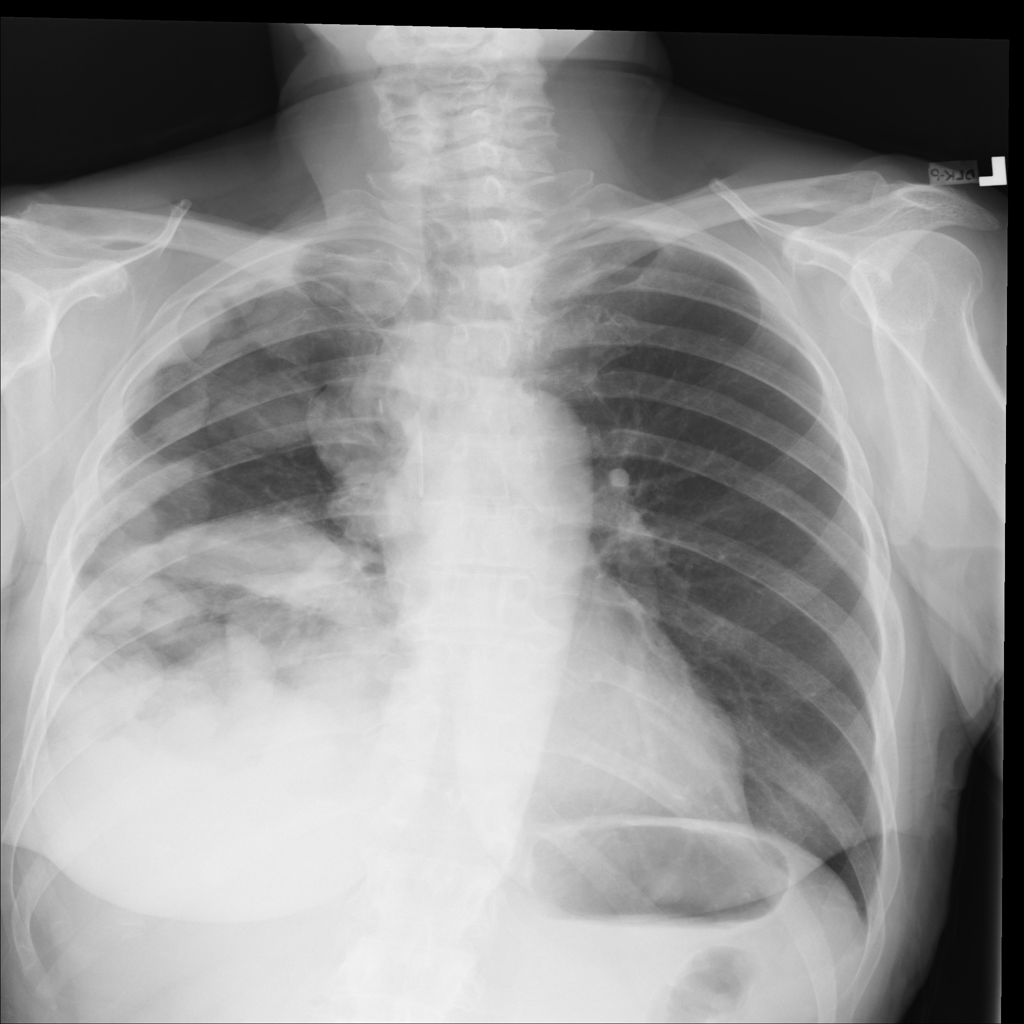

Mass

A mass is a larger focal opacity or lesion seen on the image. It is a descriptive finding that can have several causes and usually needs more imaging or clinical context to characterize.

PAT-50E5 · IMG-008Mass

PAT-50E5 · IMG-008

PA